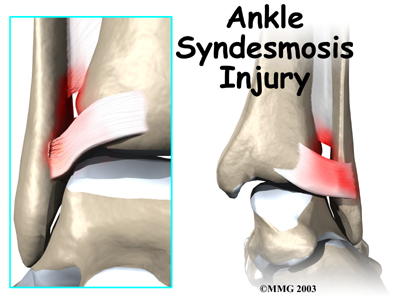

An ankle injury common to athletes is the ankle syndesmosis injury. This type of injury is sometimes called a high ankle sprain because it involves the ligaments above the ankle joint. In an ankle syndesmosis injury, at least one of the ligaments connecting the bottom ends of the tibia and fibula bones (the lower leg bones) is sprained. Recovering from even mild injuries of this type takes at least twice as long as from a typical ankle sprain.

Mild syndesmosis sprains usually involve a stretch or slight tear in only one of the ligaments making up the syndesmosis. Moderate tears of the ankle syndesmosis may lead to ankle joint instability, which make the ankle mortise loose. In severe tears of the ligaments, the ends of the tibia and fibula actually spread apart. This condition is called diastasis.